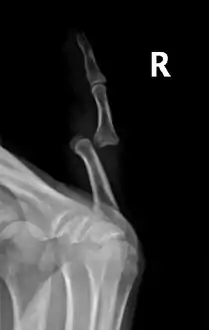

• Finger: Interphalangeal (IP) or metacarpophalangeal (MCP) joint dislocations[31]

• In the United States, men are most likely to sustain a finger dislocation with an incidence rate of 17.8 per 100,000 person-years.[32] Women have an incidence rate of 4.65 per 100,000 person-years.[32] The average age group that sustain a finger dislocation are between 15 and 19 years old.[32]